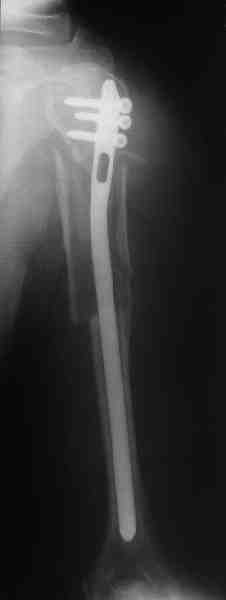

Уважаемые коллеги.

Прооперировали больную с переломом плеча все же гвоздем, Фото в приложении.

Интересно, а канал рассверливали?

Гвоздик похоже ЦИТОвский?

Полагаю, бабушку можно поздравить с обретением

независимости. Судя по снимкам, неврологических расстройств нет и такая пациентка выпишется после снятия швов.

Какие рекомендации Вы дадите этой женщине на ближайшие 6 месяцев?

> Интересно, а канал рассверливали?

минимально

> Гвоздик похоже ЦИТОвский?

точно

НЗ> Интересно, а канал рассверливали?

Только сформировали канал в головке. Диафиз не рассверливали. Хотя при необходимости, конечно, рассверлили бы.

НЗ> Гвоздик похоже ЦИТОвский?

Гвоздь большеберцовый нашей модификации, действительно, их делает предпричятие "ЦИТО". Тут взят 9 мм, укорочен до 240 мм, сделано дополнительное отверстие самое проксимальное, ну и для дистального винта.

НЗ> независимости. Судя по снимкам, неврологических расстройств

НЗ> нет и такая пациентка выпишется после снятия швов.

Неврологии нет, а выписать можно хоть на второй день, швы можно снять и в местной больнице.

НЗ> Какие рекомендации Вы дадите этой женщине на ближайшие 6 месяцев?

Почему так надолго? На ближэайшие недели - разработка движений, и все. Полагаю, что недель после 4 никаких рекомендаций не будет нужно, просто жить обычной жизнью сельской пенсионерки.